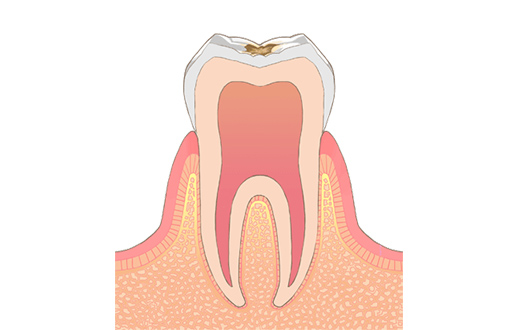

C1初期う蝕

一般的に初期むし歯と言われています。ごく浅い、エナメル質という歯の一番外側に限局した虫歯です。機能や審美的に問題がなく、虫歯の進行が認められなければ、治療は必要ありません。初期むし歯になってしまった部分は虫歯が進行しやすいため、より丁寧なブラッシングが必要になります。